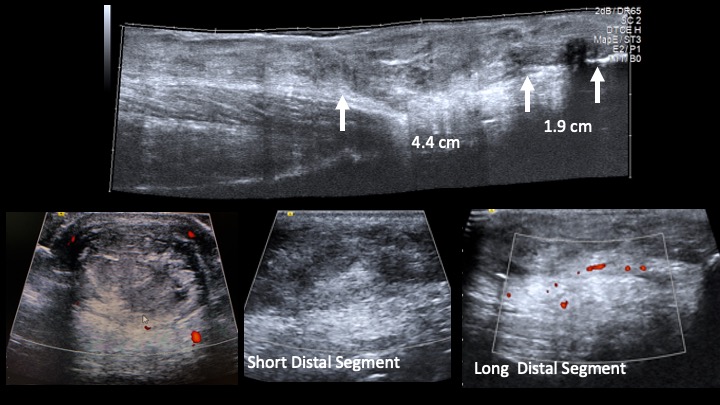

Please review the ppt which includes the Cine during ACTIVE ROM. Then MRI from today. I don’t understand the apparent discrepancy. I thought there was a low grade partial tear 1.9 cm prox to insertion on US (I scanned). But during dynamic imaging the distal segment didn’t move at all….so I wondered if there was […]